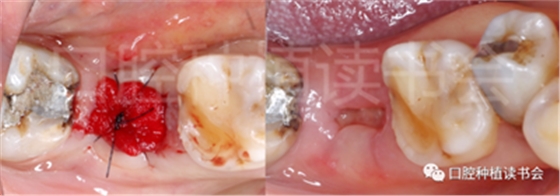

圖1 無(wú)法保留的上頜隱裂后牙,拔牙后即刻種植。

患者為70歲女性,右下后牙樁核冠因遠(yuǎn)中牙根縱裂脫落,全身健康狀況良好,輕度骨質(zhì)疏松??趦?nèi)檢查:47殘根,遠(yuǎn)中根縱裂,部分根面已腐至齦下2mm,叩(++),松(-);48近中傾斜阻生,咬合關(guān)系、修復(fù)間隙及牙周情況正常(圖12)。

圖12 遠(yuǎn)中根縱裂及根面齲導(dǎo)致47殘根無(wú)法保留。

術(shù)前CBCT(美亞光電)檢查:47根分叉下方骨高度及骨寬度滿足即刻種植要求(圖13)。

圖13 47根分叉區(qū)骨寬度及骨高度(與下頜神經(jīng)管之間的距離)滿足即刻種植要求。